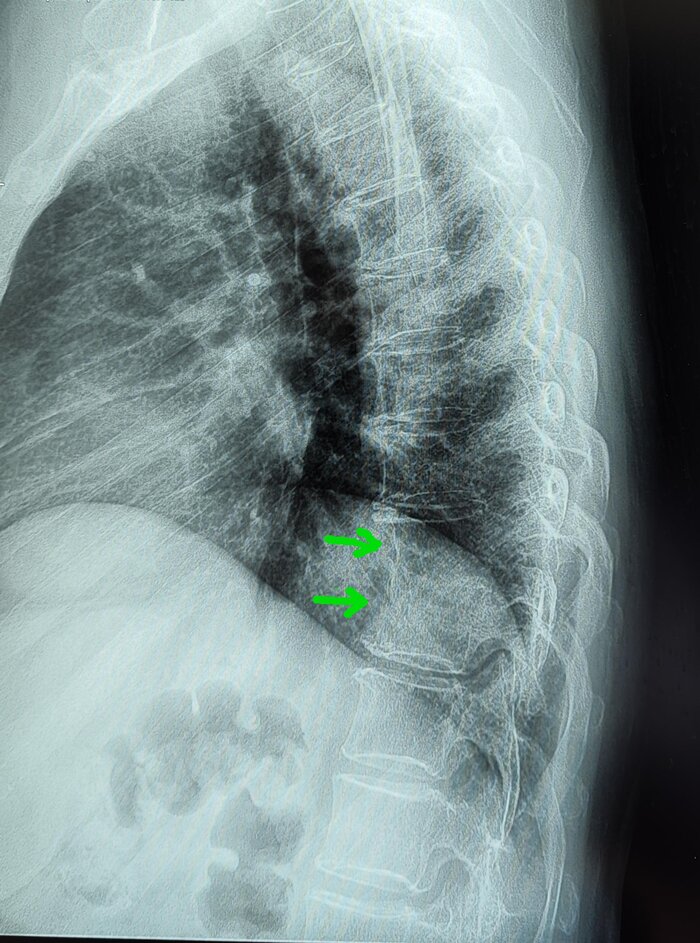

Основной метод — рентгенография позвоночника в боковой проекции. Критерии диагноза:

Клиновидная деформация (сужение передних отделов) как минимум трёх смежных позвонков.

Угол грудного кифоза более 45° (в норме 20-40°).

На МРТ- снижение высоты передних отделов тел Th6,7,8 позвонков(клиновидная деформация).

На Р-грамме грудного отдела позвоночника(стоя) в боковой проекции, визуализируется гиперкифоз грудного отдела позвоночника 4 ст. по Коббу. Аналогично с данными МРТ , снижение высоты передних отделов тел Th6,7,8 позвонков(клиновидная деформация).

Итоговый диагноз: Патологический гиперкифоз грудного отдела позвоночника 4 ст. по Коббу. Клиновидная деформация тел Th6, Th7, Th8 позвонков, как следствие перенесенной остеохондропатии, соответствует болезни Шейермана-Мау.S-образный сколиоз 2ст.Остеохондроз грудного, поясничного отделов позвоночника.